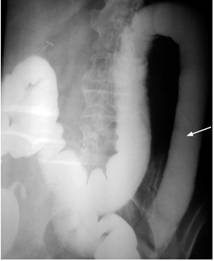

Por la posibilidad de tratarse de un cáncer de colon y ser la causa de la DM se realizó una colonoscopia que mostró mucosa eritematosa, friable en una superficie granular con patrón vascular normal. Se tomó una muestra para el estudio histopatológico en el que se encontró linfocitos intraepiteliales difusos dispersos, cuerpos apoptóticos en células epiteliales superficiales, metaplasia de células de Paneth, incremento celular mononuclear en la lámina propia y en el estudio inmunohistoquímico: CD8+ >25 % de las células. Todos estos hallazgos son compatibles con una CU (Figura 6 A y B).

Como se pudo llegar con mucha dificultad al colon izquierdo y tomar la biopsia, se practicó un enema opaco (Figura 7) y los hallazgos coincidieron con los reportados por la colonoscopia, negando la posibilidad de una neoplasia.

La CU ocurre en la mayoría de los casos entre la tercera y séptima década de la vida 7, esta paciente tenía 70 años. Cabe recordar que aún no se conoce su causa y el mecanismo por el cual se produce el daño hístico 8. El diagnóstico de esta paciente se fundamentó en los criterios de Mendeloff 9: historia de diarreas o sangramientos rectales por 6 semanas o más, sigmoidoscopia que revele friabilidad de la mucosa con sangramiento al contacto o hemorragias petequiales con inflamación de la mucosa, enema de bario con evidencias radiográficas de ulceración, estrechamiento o acintamiento del colon y alteraciones macroscópicas o microscópicas características. Todas estas alteraciones estaban presentes en este caso.

En relación con las complicaciones colónicas, se estima que el riesgo de cáncer colorrectal en la CU es de 4 a 20 veces mayor que en la población general 7. Por ello, teniendo en cuenta la posibilidad de esta complicación, se realizaron todos los estudios para descartar la enfermedad, y se diagnosticó la CU por estudios endoscópicos, imagenológicos e histológicos.